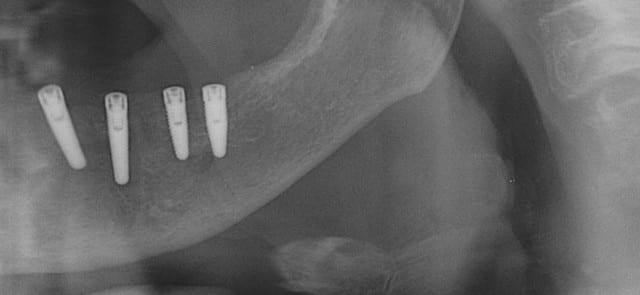

Ainsi donc je fais du ridge split, sans le savoir.

Je ne connais pas trop les appellations techniques, de ce que je fais ce qui m'évite de croire que c'est compliqué!

Pour ce cas j’ai effectivement quelques radios.

mais sur cet ordi je ne peux te passer que les panos

Copie de vi p01.07 - Eugenol

Copie de vip  050220081 givypi - Eugenol

Merci pour les radios.

Tu as placé quoi dans l'autre secteur (En bas à droite ?)

L'angulation de l'implant antérieur semble un peu...

trop angulé ?

Tu prévois quoi comme restauration ?